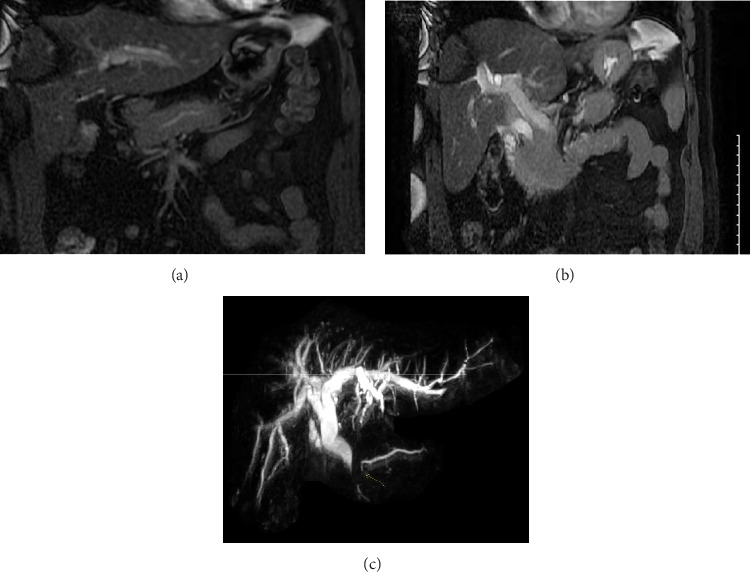

Introduction: Autoimmune pancreatitis (AIP) and pancreatic cancer are top differentials of obstructive jaundice originating from the pancreas. Case Description/Methods: The patient's findings were concerning for malignant biliary obstruction, but a thorough workup determined that the patient had AIP-NOS. She underwent EBS and was discharged on a steroid taper. Follow-up demonstrated complete resolution of symptoms, laboratory markers, and imaging. Conclusion: Adequate pancreatic tissue is not always obtained with 22-gauge needles. Biliary stenting is justifiable in AIP with significant hyperbilirubinemia. It is important to consider AIP for with a pancreatic head mass and obstructive jaundice to optimize outcome.

Abstract Image